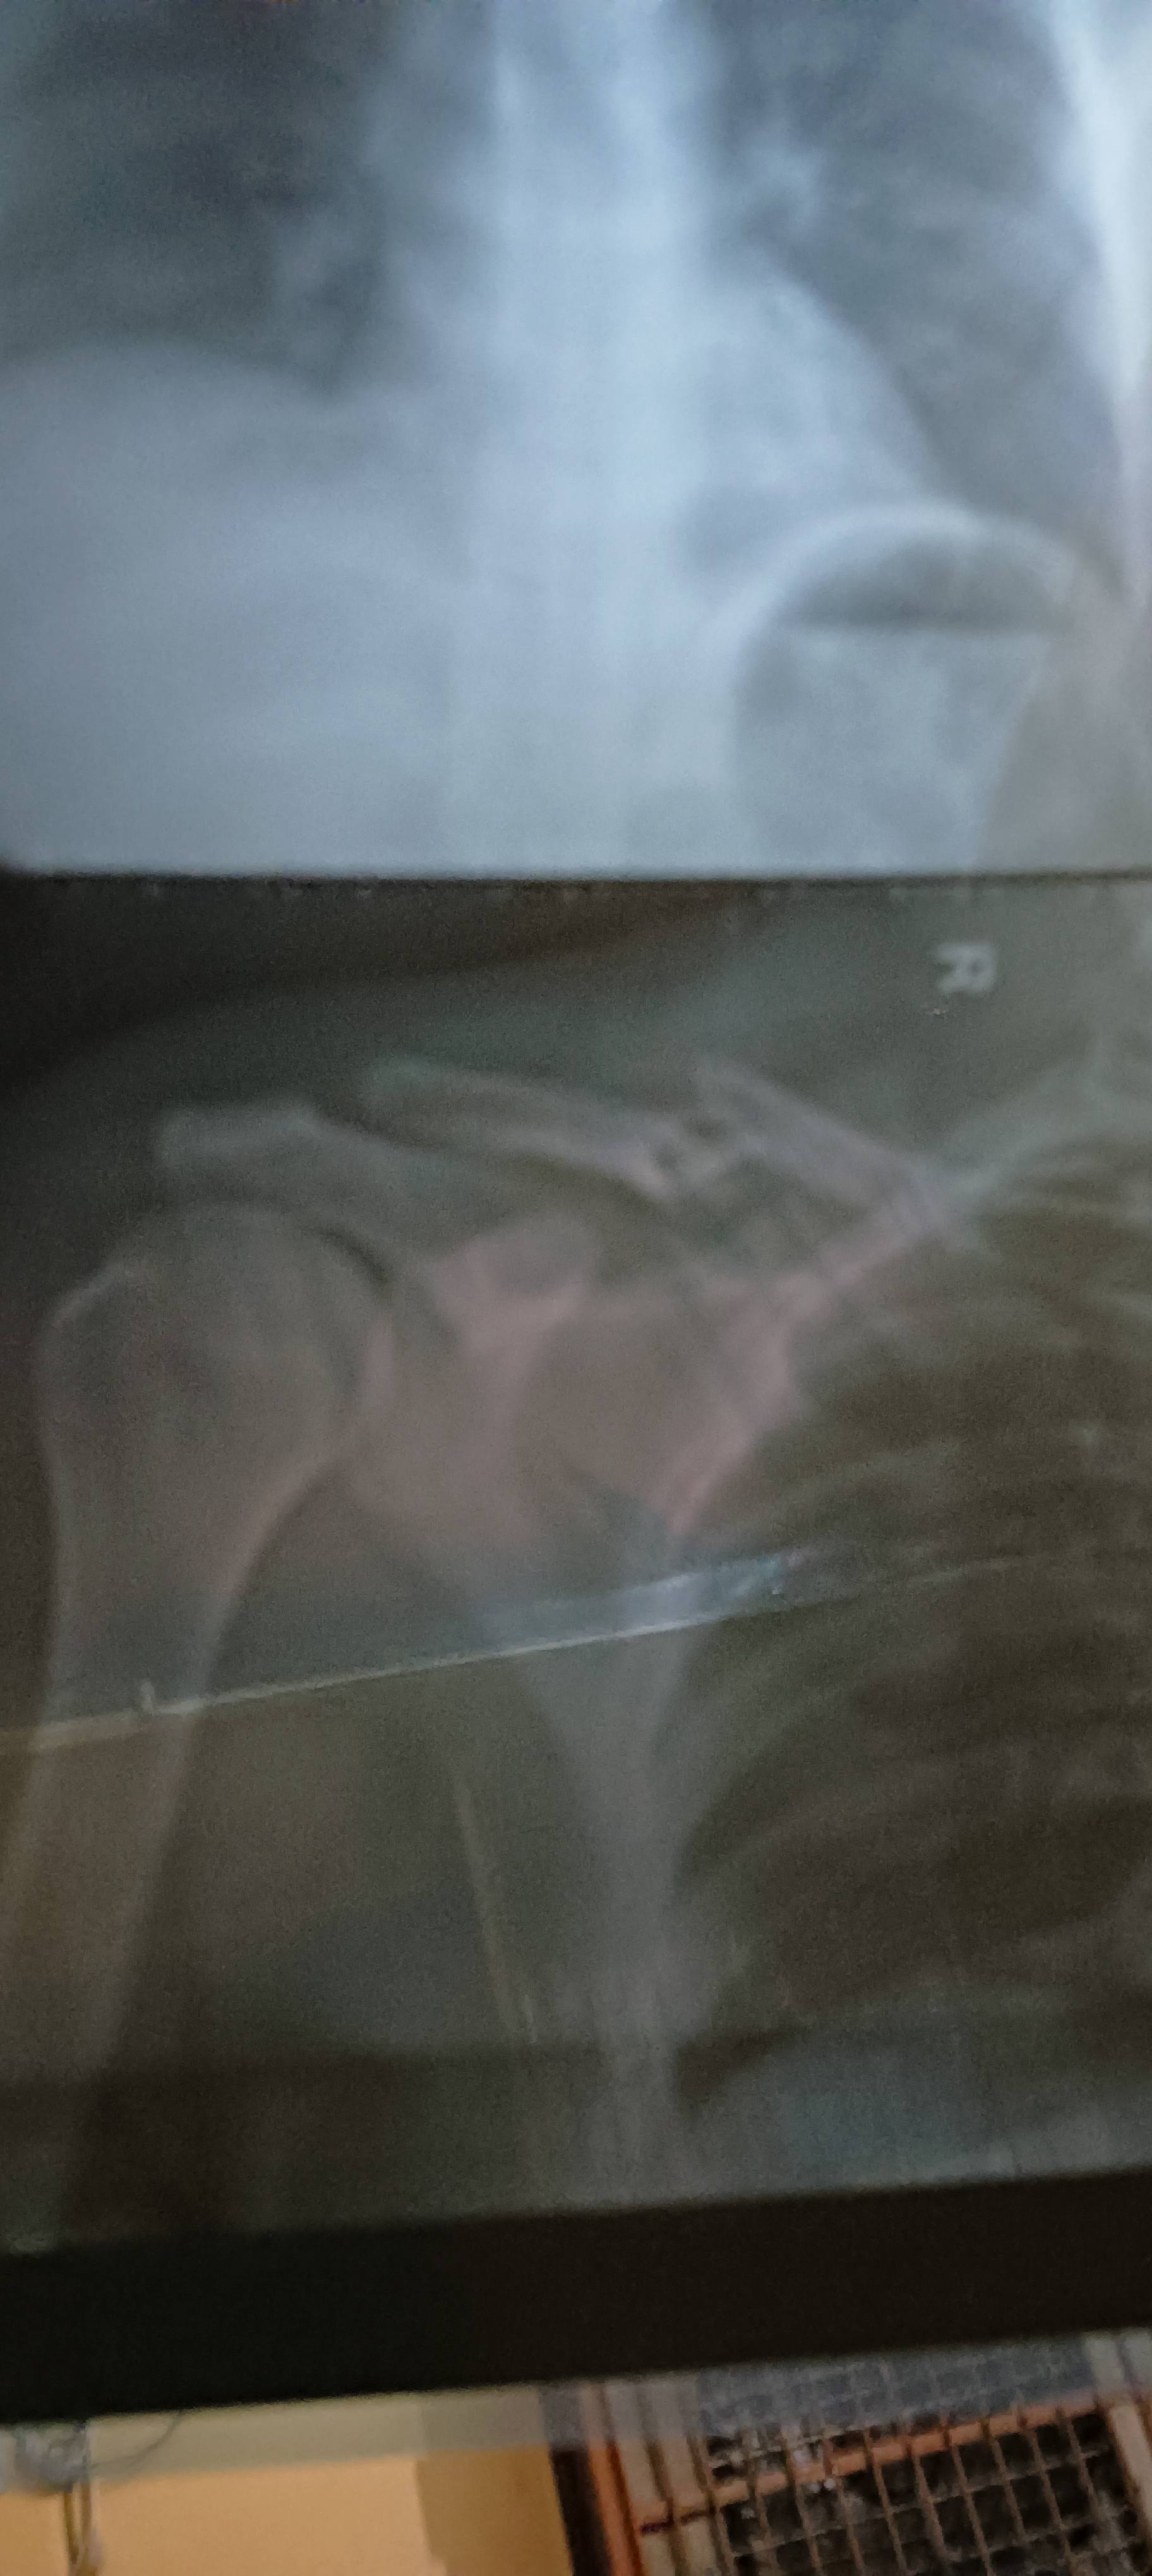

sir kitne time me tik hoga & kon kon si excercise karu

Please ? tell me Kitana time lagta hai thik hone m